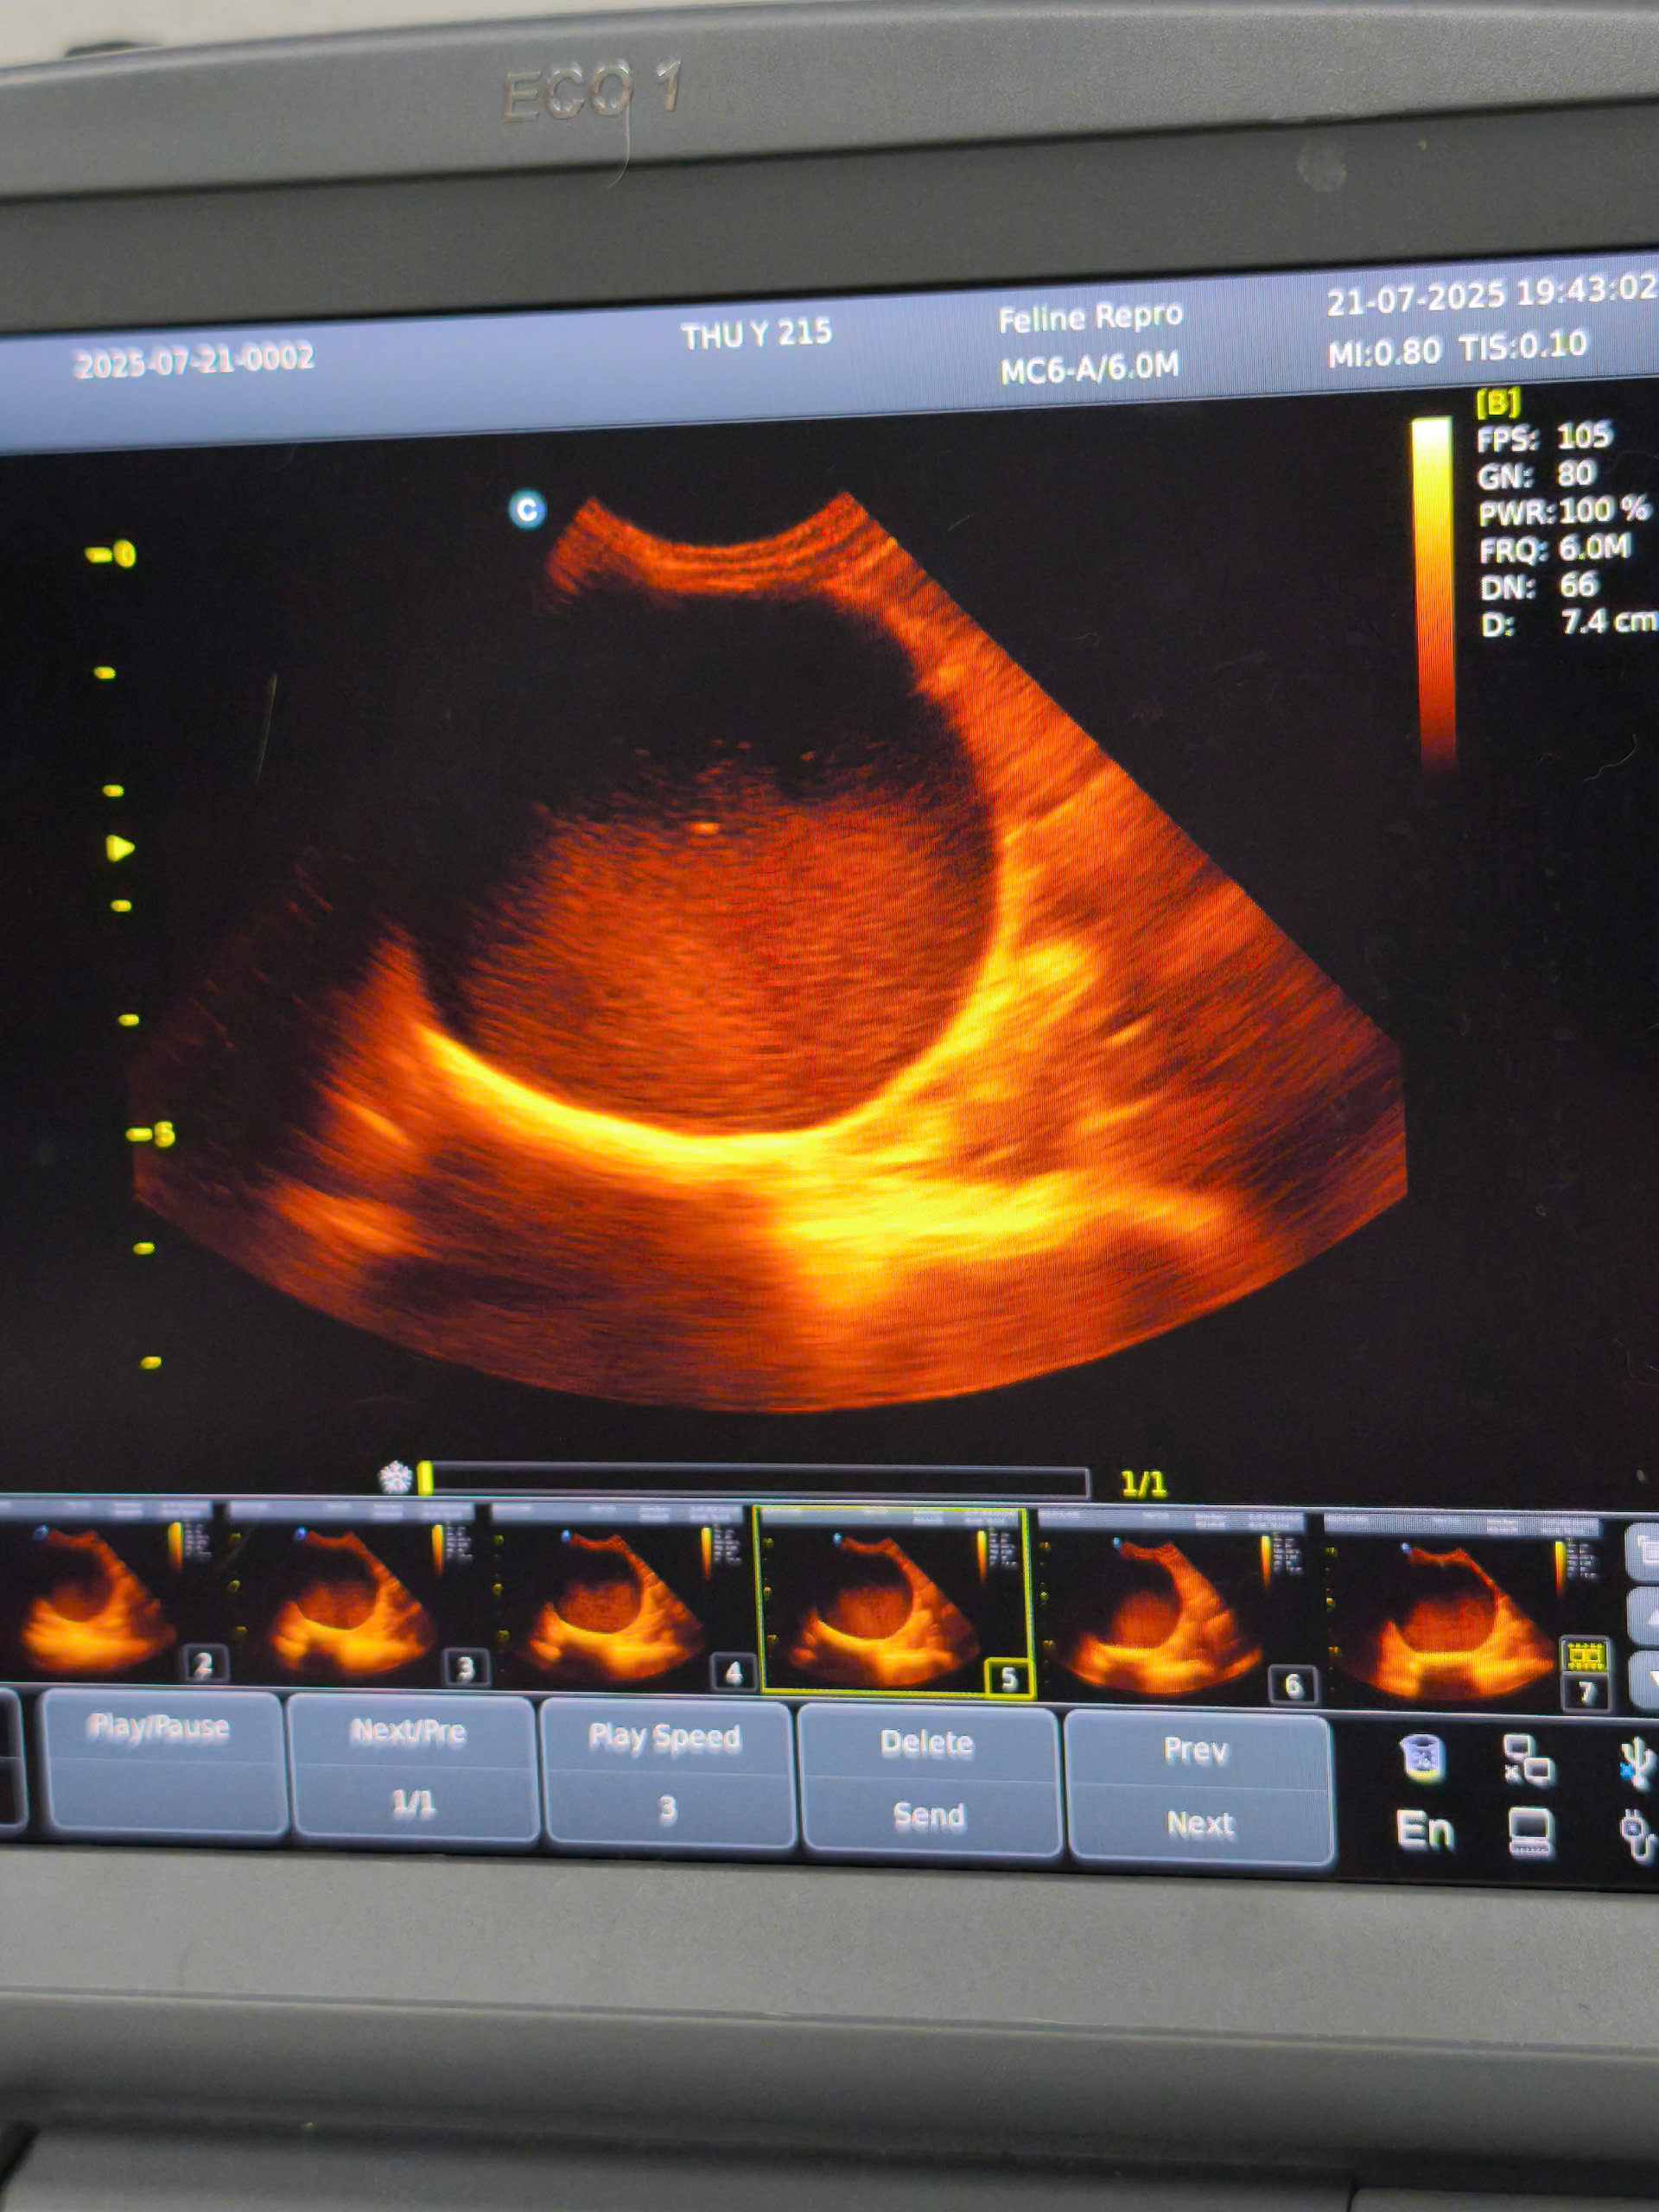

PHẪU THUẬT VIÊM TỬ CUNG Ở BÉ MÈO MIMI